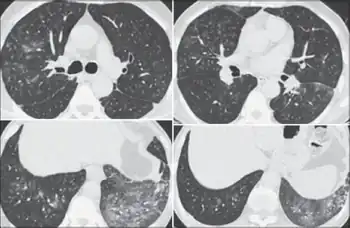

It can be difficult to accurately diagnose a patient with byssinosis due to symptoms that are similar to other respiratory diseases such as chronic obstructive pulmonary diseases (COPD), asthma, or bronchitis.[6] Byssinosis can be misdiagnosed as other pneumoconioses therefore a chest x-ray and/or lung function test is needed to accurately diagnose a patient who may have byssinosis.[6] The main distinction of byssinosis from other respiratory diseases comes from the initial exposure. Patients who have byssinosis have typically been exposed to cotton or just dust for an extended period of time and experience symptoms of chest tightness and coughing.[5]

Patient history should reveal exposure to cotton, flax, hemp, or jute dust. Measurable change in lung function before and after working shifts is key to diagnosis. Patients with byssinosis show a significant drop in FEV1 over the course of work shift. Chest radiographs show areas of opacity due to fibrosis of the pulmonary parenchyma.